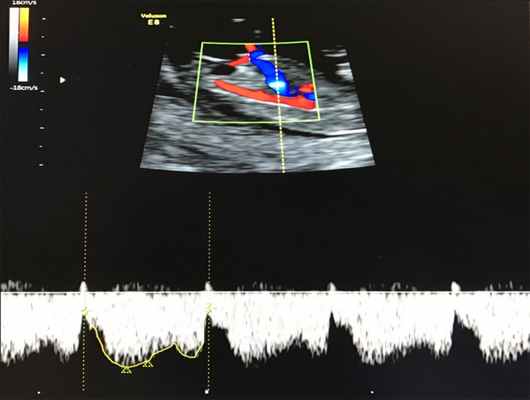

- кровоток в венозном протоке – это маленький сосуд в печени плода. При обратном (ретроградном) токе крови в данном сосуде можно предположить, что у плода хромосомный синдром, либо врожденный порок сердца.

Нормальный кровоток в венозном протоке

Но важно правильно получить этот кровоток и дать ему оценку. Для этого требуются определенные навыки и квалификация врача, которые подтверждаются ежегодной сертификацией FMF.